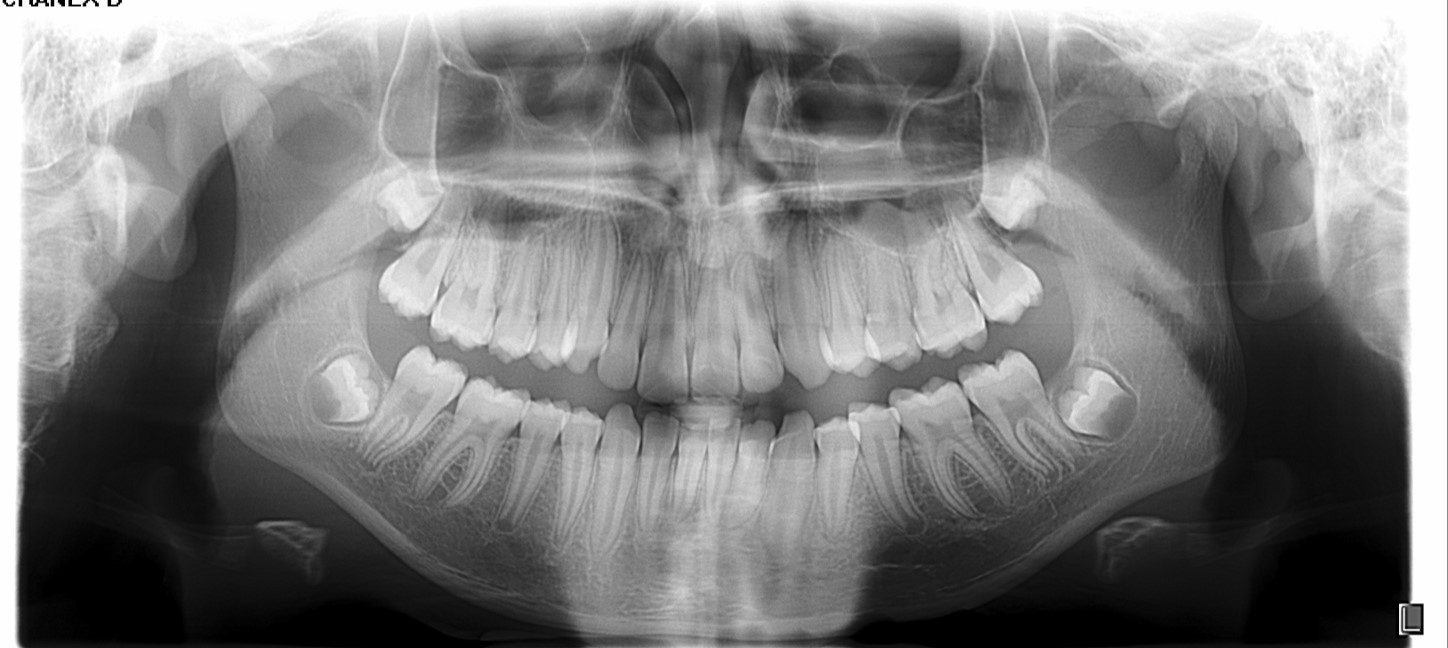

Chief complaint: We present the case of a 12-year-old female patient who came for an orthodontic evaluation, motivated by a family history of treatment. Clinical and radiographic analysis revealed a skeletal Class II malocclusion with molar and canine relationships also in Class II, moderate crowding in both arches, a deviation of the dental midline, and ectopic eruption of tooth 13. No functional issues with breathing or swallowing were observed, and oral health was generally good. A slight mandibular retrusion was noted in the soft tissue profile. A treatment plan was proposed using the Angel Aligner Pro system, aiming to correct dental misalignments and improve facial harmony through a minimally invasive, growth-adapted approach.

- Moderate upper and lower crowding

We approached the case by combining upper distalization using the A8 protocol with an asymmetric virtual jump. In this way, we solved the crowding without proinclining the incisors and improved the anteroposterior relationship through the use of elastics. In the lower arch, we carry out a development of the posterior sectors prior to the resolution of the crowding, in order to avoid roundtripping and excessive IPR of the incisors. To achieve an effective extrusion and distalization of 13, we combine the use of direct bonding button on vestibular of 13, with angelButton elastics mesial and distal to the canine. These mechanics help to ensure that the extrusion is real and that the aligner always remains adapted.

In the upper arch, the main goal will be to correct the Class II malocclusion by distalizing the upper posterior teeth in order to resolve crowding without proinclining the incisors. This movement will be accompanied by an asymmetric “bite jump” of 1 mm, which will help improve the skeletal Class II discrepancy, promoting mandibular projection, especially considering that the patient is still in the growth phase. Additionally, bilateral and symmetric expansion will be planned until a torque of 0° is achieved, allowing for proper transverse alignment and greater stability of the final result. Lingual button cutouts will be placed on teeth 14 and 24 to facilitate the required movements. To optimize control and retention, vertical mesial beveled attachments, as large as possible, will be placed on the premolars and molars, as well as on teeth 12 and 22, reinforcing the mechanics in the anterior sector. The inclination of the central incisors 11 and 21 will be corrected according to the visual reference provided in the clinical image. Furthermore, it will be necessary to center the upper midline by shifting it 0.5 mm to the left to achieve greater aesthetic symmetry. As for the lower arch, treatment will begin with a phase of expansion and derotation of the posterior teeth, which will set the stage for subsequent movements in the anterior sector. Once this goal is achieved, alignment of the teeth from canine to canine will proceed, aiming to minimize anterior interproximal reduction (IPR) and avoid unnecessary round- tripping movements of the incisors. Vestibular button cutouts will be made on teeth 36 and 46, while teeth 37 and 47 will have horizontal attachments that will serve as anchorage to ensure stability during treatment.